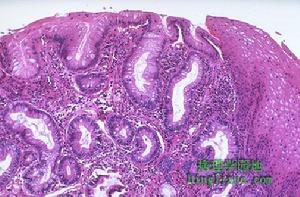

2.內鏡表現白塞病的腸管潰瘍好發於回盲部,結腸鏡檢查最有意義。潰瘍多發生於腸系膜附著的對側,呈圓形、小而深的潰瘍,有多發及穿孔的傾向。仔細觀察,小腸鏡對發現小腸潰瘍有幫助,小腸潰瘍和大腸潰瘍的外觀形態不同。小腸潰瘍小而深,常多發,黏膜向潰瘍集中,潰瘍的周邊隆起不明顯,潰瘍為邊緣非常清楚的圓形鑿出樣的急性潰瘍,在潰瘍底部不附有白苔,大多在2cm以下,亦有直徑大到2~3cm者;內鏡可見對向潰瘍中心部的黏膜明顯集中,潰瘍周邊形成明顯隆起,為環堤狀。潰瘍呈不規則的下陷,看上去很似Borrmann2型或Borrmann3型癌的形態。單憑潰瘍的形態與回盲部單純潰瘍難以區分。X線檢查常在回盲部發現黏膜集中的潰瘍龕影。病變部腸管的黏膜可出現狹窄以及小腸和結腸的張力增加等。